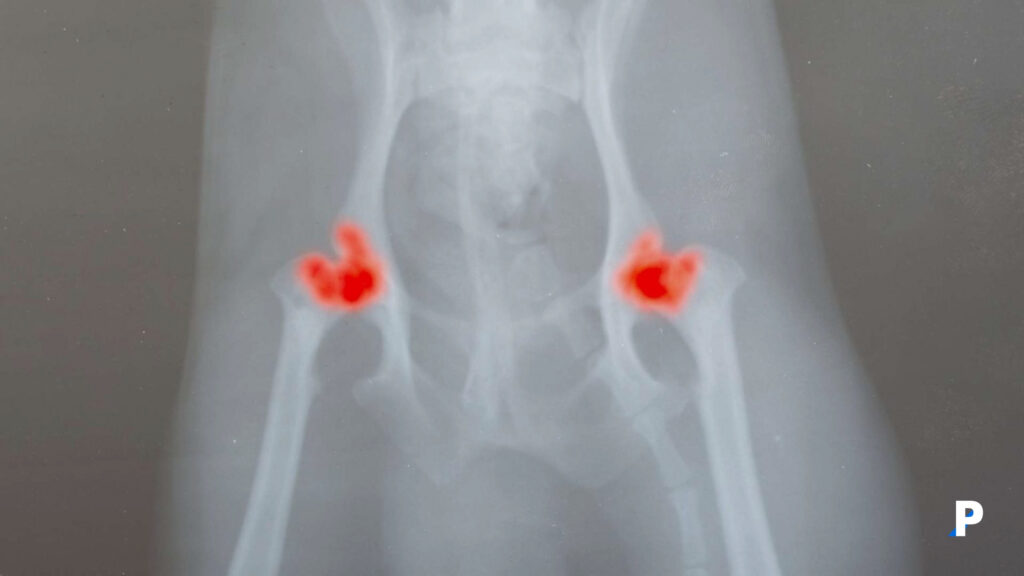

1. Kalça Displazisi

Kalça displazisinin Alman Çoban Köpekleri ve ilgili köpek ırklarını etkilediği yaygın olarak bilinse de, Saint Bernard’lar (neredeyse %50 oranında görülme sıklığına sahip) gibi birçok büyük köpek ırkı yüksek risk altındadır. Bunun nedeni, günümüzün büyük ve dev ırklarının daha hızlı büyümesi ve iskeletlerinin eş zamanlı büyümesini geride bırakan kas kütlesi kazanmasıdır. Büyümelerindeki dengesizlik, kalça eklemindeki ağırlık dağılımını değiştirir ve kalça eklemi etrafındaki kemiklerin oluşumunu değiştirir.

Ne yazık ki, köpeklerin gelişigüzel yetiştirilmesi, zamanla kalça eklemlerinde ciddi artrit geliştiren birçok büyük ırk köpek için bunu kalıcı bir rahatsızlık haline getirmiştir. Düşük kaliteli üreme stokları da bunu birçok küçük ırkta da yaygın bir bulgu haline getirmiştir.

Tüm büyük ırk köpeklerde kalça displazisi görülmez. Üreme köpekleri ve damızlıklarını Ortopedik Hayvanlar Vakfı uzmanları tarafından radyografik olarak değerlendiren saygın yetiştiriciler vardır. Bu uzmanlar kalça değişikliklerinin yokluğu veya ciddiyeti hakkında sertifikalı raporlar sunarlar. Büyük ırk bir köpek yavrusu satın almakla ilgileniyorsanız ve kalça displazisi ve sonrasında oluşan osteoartritin köpeğinizi gelecekte sakat bırakmayacağından daha iyi emin olmak istiyorsanız saygın bir yetiştirici bulun ve ebeveynlerin kemik gelişim raporlarını görmek isteyin. Öncelikli tavsiyemiz, herhangi bir köpek satın almamanız ve sahiplenmeniz olacaktır. Özellikle mix ırk olarak adlandırılan kırma cins köpeklerde bilinen veya bilinmeyen hastalıkların çıkması çok daha düşük olasılıktır.

Kalça displazisini erken teşhis edebilirseniz, kalçanın normal açısını geri kazandırabilecek ve kalça displazisinin etkilerini hafifletebilecek kalça ameliyatları vardır. Ne yazık ki, köpeklerde kalça displazisi vakalarının çoğu bu tür ameliyatlar için çok geç teşhis edilir (ve pahalıdır), bu da sakat hayvanlar için tıbbi tedavi veya kurtarma ameliyatlarını tek seçenek haline getirir. Etkilenen hayvanlar için kilo yönetimi (zayıf tarafta kalmak) da yardımcı olacaktır.